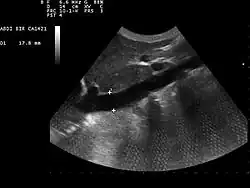

Echographie abdominale montrant la veine cave inférieure, les croix sont positionnées sur ses parois

Dans les services de réanimation, la mesure de la variabilité respiratoire du diamètre de la veine cave inférieure par échographie permet d'évaluer la volémie, et donc de prédire la réponse à l'expansion volémique, au cours de la prise en charge d'une instabilité hémodynamique chez un patient sous ventilation mécanique[1],[2].